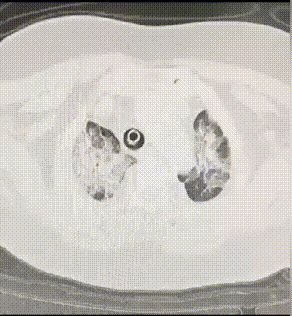

因为叫“沉默性缺氧”所以表面上很难看出来有什么不正常的,但是如果通过血氧仪测试,会发现血氧饱和度低于90%。

据武汉市第四医院武胜路院区心内一科主任成忠介绍,目前科室里大量危重患者都是感染新冠病毒后出现严重缺氧,甚至血氧饱和度低于70%。其中以七八十岁的老人最多。这部分患者却没有明显感觉到胸闷、呼吸困难等。此时,家人和病人容易忽视病情,等病情恶化送医时,往往很严重。专家表示,这种现象可以称为“沉默性缺氧”,外表看起来毫无波澜,其实已经非常危险了。医生提醒,相较年轻人,老年人对机体异常反应不明显,因此,老人感染新冠后,家人一定要加强监测,重点关注老人体温、心率、脉搏以及外周血氧饱和度的变化,有老人的家庭可考虑备一个血氧仪,人体正常血氧饱和度在94%以上,低于这个数值就要引起警惕。 专家表示老人在家里配备血氧仪十分有用。对于本身有心肺基础病的人,感染之后肺炎加重,血氧就会下降,血氧仪可以帮助监测血氧情况。因为有的老人本身感知不那么灵敏,本身缺氧但是他没有重视,只是觉得有点喘,这种情况下,血氧仪就比较客观。家人可以根据具体数据决定是否就医。